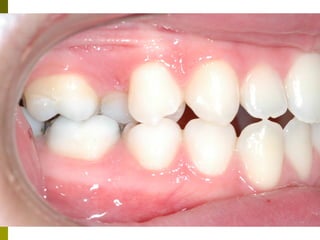

Πρώτη σχολική ηλικία 6-10 ετών

   Αρχίζει αλλαγή των τομέων και η ανατολή των

πρώτων μόνιμων γομφίων (μεικτή οδοντοφυΐα)

   Παρατηρούμε η αλλαγή δοντιών να γίνεται με τη

σωστή σειρά και στη σωστή θέση

   Μπορεί να χρειαστεί πρώιμη ορθοδοντική

θεραπεία, για να αποφευχθούν πιο δύσκολες και

πολύπλοκες εργασίες αργότερα

   Διατήρηση νεογιλών δοντιών στον οδοντικό

φραγμό μέχρι τη φυσιολογική τους απόπτωση

Μόνιμη οδοντοφυΐα 10 + ετών

 Παρακολουθούμε την ολοκλήρωση

αλλαγής δοντιών

 Ελέγχονται ορθοδοντικές ανωμαλίες

 Θεραπευτική αντιμετώπιση μονίμων

δοντιών

 Καλό προληπτικό πρόγραμμα,

εξατομηκευμένο